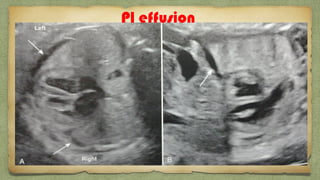

Lung:

Homogenous

echogenic tissue

Separated by

hypoechoic

domeshaped

diaphragm

Hypoechogenic structure

other than heartโ€ฆ.

CCAM

Pul Hypo

CDH

Pl effusion